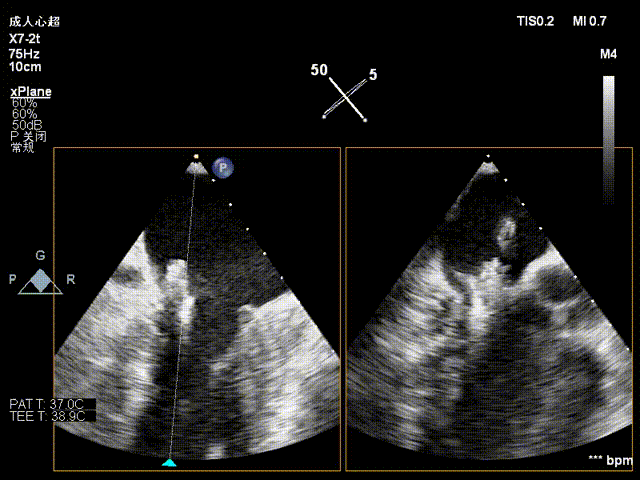

术前影像

二尖瓣后瓣腱索断裂并脱垂及关闭不全(重度)